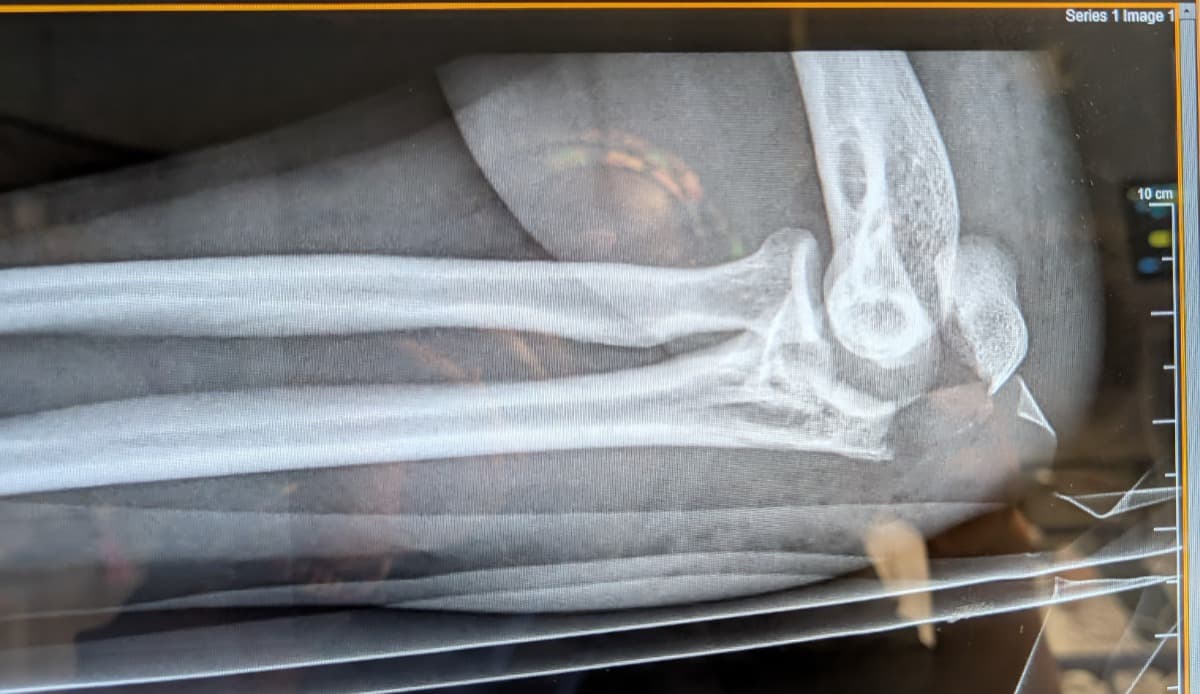

My shattered elbow